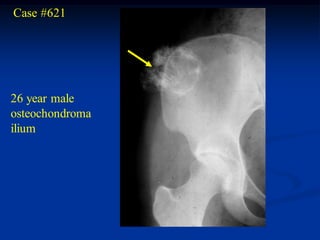

Case #621

26 year male

osteochondroma

ilium

cap

Cut specimen in path lab